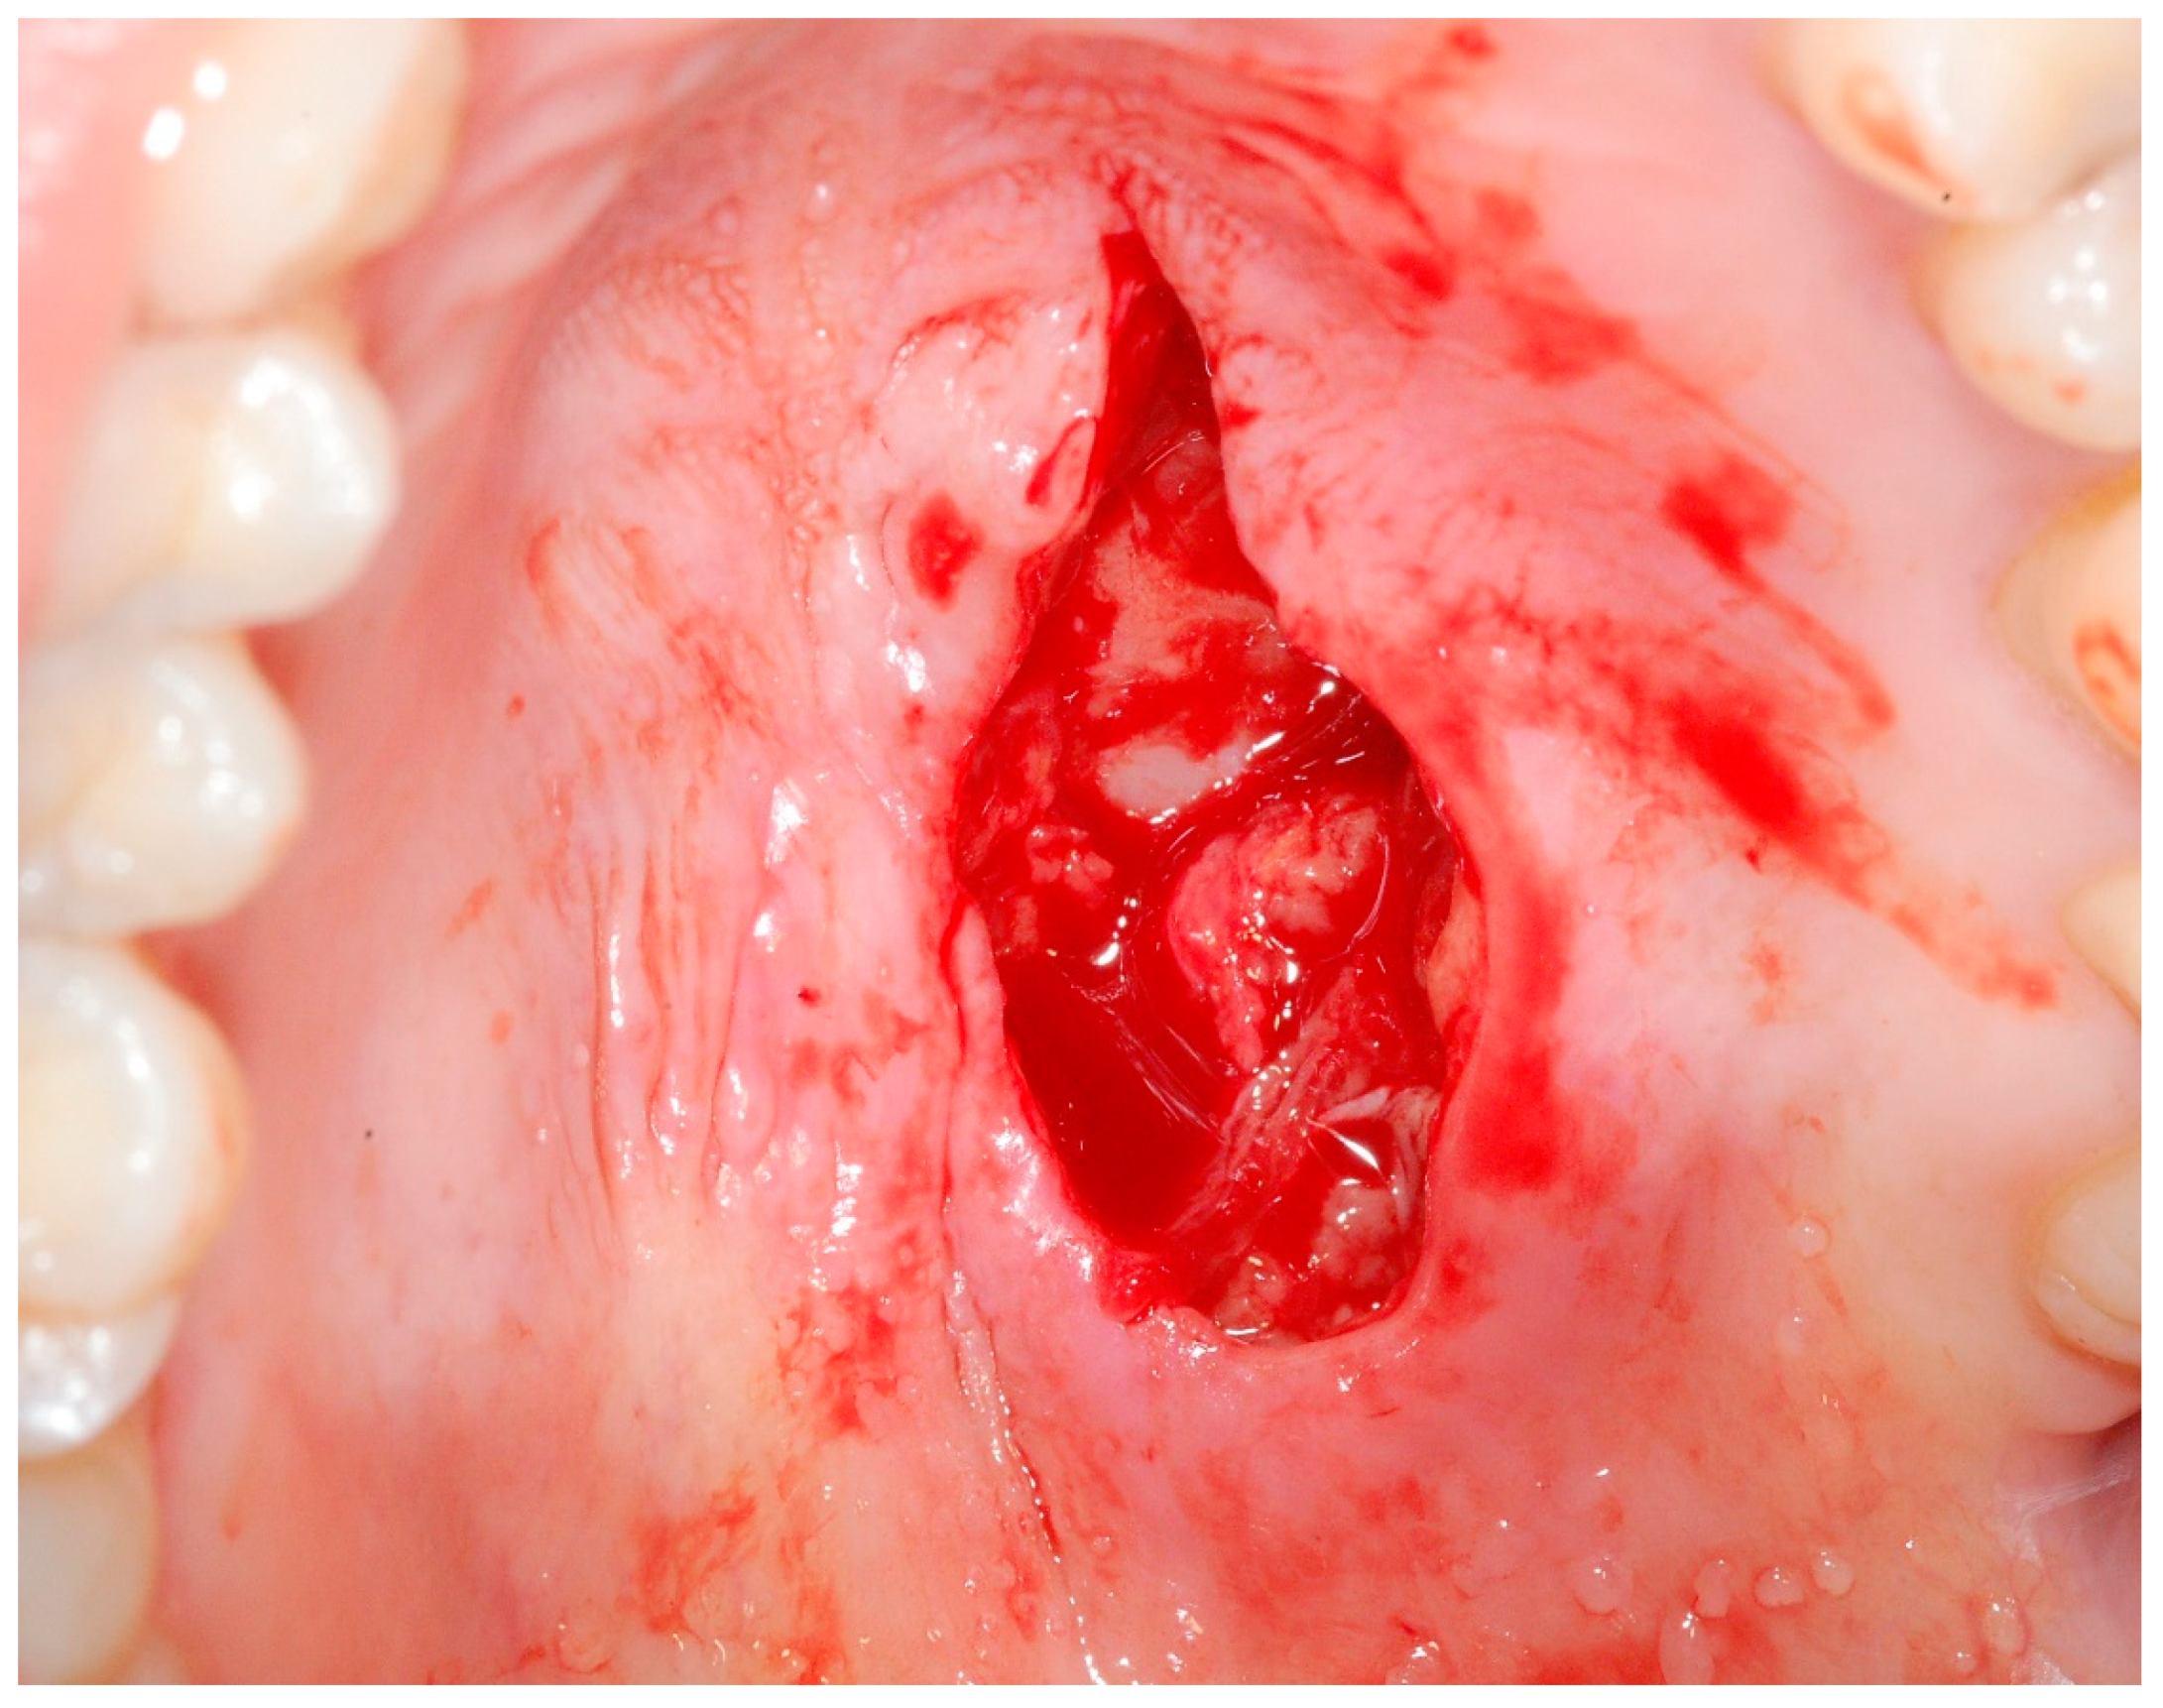

2. Case Report